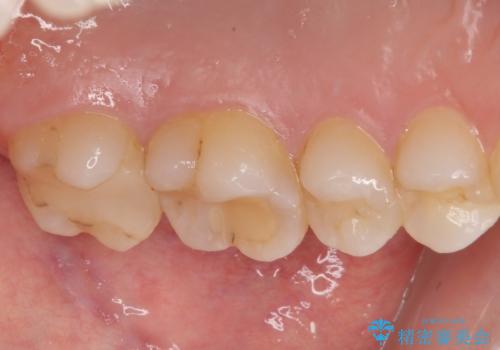

- 大学病院で「詰め物の下に虫歯がある」と言われたことを主訴に来院された患者様です。たまにしみる感じがするとのことでした。

レントゲン上で詰め物とご自身の歯の間に隙間を認めました。

拡大鏡視野下で詰め物と虫歯の除去を行い、詰め物の範囲が大きかったためオールセラミッククラウンに適した形に整えました。